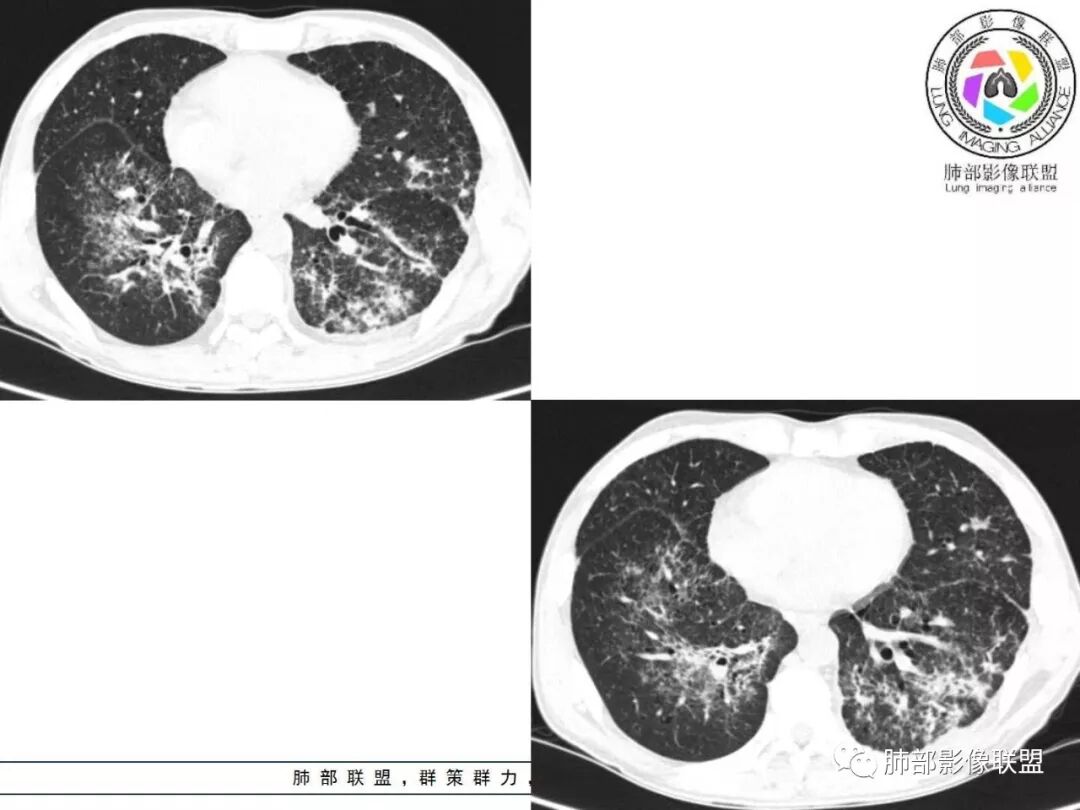

胸部CT:两肺弥漫病灶,磨玻璃影,少许实变,部分累及胸膜,磨玻璃区可见囊?少许胸腔积液,两肺可见结节,支气管血管束增粗,小叶间隔增厚,支气管走形有扭曲扩张,可见纤维化。气肿、大泡。考虑:感染性病变,PCP?查下HIV,CD4,G等。鉴别结核、结缔组织病肺浸润。

患者中年男性,发热1月,体温38℃-39℃,峰值40℃,无畏寒、寒战,伴黄痰,CRP升高明显,降钙素原稍升高,血沉、血糖正常。胸部CT:两肺弥漫病变,磨玻璃影+点片渗出,部分累及胸膜,磨玻璃区边界清楚,少许胸腔积液,两肺支气管血管束增粗,小叶间隔增厚,部分支气管走形有扭曲扩张,可见肺气肿、右肺尖肺大泡及部分纤维化改变。综合考虑:感染性病变。结核或PCP可能性大,鉴别风湿免疫、结缔组织疾病肺浸润和腺癌等恶性病变。

胸部CT:两肺弥漫病灶,中央间质分布为主,部分位于胸膜及叶间裂旁,磨玻璃影,斑片影,部分实性结节,肺气囊,支气管血管束增粗,小叶间隔增厚,叶间裂不均匀增厚,支气管走形有扭曲扩张,可见纤维化、气肿、大泡。考虑:LIP加MALT。鉴别PLCH、PCP、结核、结缔组织病肺浸润。

双肺弥漫性病变,多发磨玻璃密度及小叶间隔增厚,大部分沿支气管血管束分布,伴支气管轻度扩张,以午后及晚上发热为主,考虑感染性病变,间质性结核可能大,另双肺多发肺气囊,LIP待排

病灶呈片状磨玻璃密度影,呈典型的烟花征。磨玻璃影密度偏高,有网结节样改变,与正常肺实质分界清楚,且常见相对高密度的勾画。

烟花征分为3肿类型:晕征、反晕征及均匀分布。

病变一般沿血管支气管束分布或小叶分布,一般上肺多于下肺(这与常见继发性肺结核分布相若)。

常会伴有其他继发性肺结核病灶,如斑片影、结节影,树芽征,新旧不等改变。

2. 肺气肿背景(小叶中心性肺气肿);双肺多发病灶整体沿血管支气管束及胸膜下分布,以上叶及下叶背段分布为主,有实变及GGO,边界清楚,有树芽,小叶间隔及中央间质增厚,叶间裂见到多发结节,部分支气管不规则牵拉扩张,提示病灶纤维化明显,结合临床病史,考虑病灶为间质性感染,肺门及纵隔内有钙化淋巴结,小叶间隔结节,考虑淋巴道增值性疾病可能,综合常规要怀疑间质性肺结核。